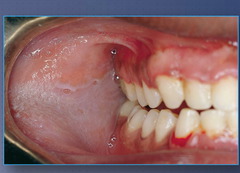

Bluish pink fluid filled nodule on lower lip caused by severance of the salivary gland a)Mucocele b)Pleomorphic adenoma c)epidemic parotitis (mumps) d)Ranula

Front

Mucocele

Back